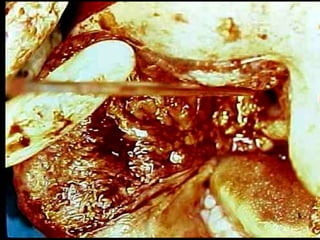

Trismus importante debido a que

El tumor ya rompió el hueso com-

Pacto de la cara interna de la

Mandíbula y empezó a tomar el

Músculo pterigoideo interno y

milohioideo.